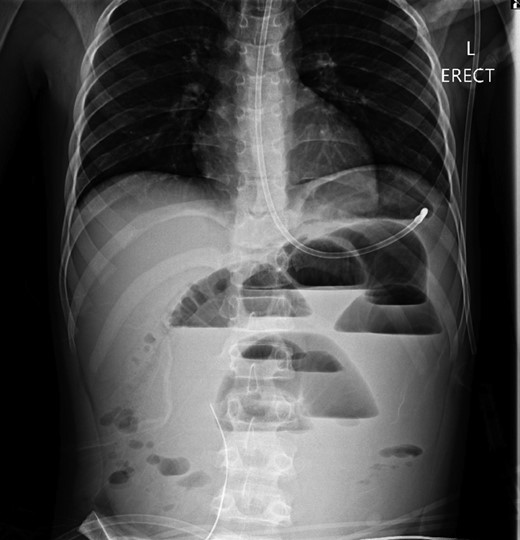

A 10-year-old boy presented unwell with generalized peritonitis after 3 days of abdominal pain, nausea and anorexia. He had a low-grade fever but all other vitals were within normal limits. Blood tests showed a raised white cell count of 16 × 109 with neutrophilia and raised C-Reactive Protein of 127 mg/l. Laparoscopy revealed generalized purulent peritonitis secondary to perforated appendicitis. Appendicectomy was performed and the appendiceal stump was secured. Lavage of the abdomen was performed with a minimum of four litres of warmed normal saline. Fluid was suctioned, an abdominal drain was placed and the pneumoperitoneum was deflated. By the second postoperative day, he developed an ileus with persistent vomiting (Fig. 1). This was managed conservatively with nasogastric intubation, bowel rest, electrolyte replacement and fluid therapy. It became clear by the fifth postoperative day that the patient had intestinal obstruction. On examination, he had a distended abdomen, with intractable nausea and vomiting. Blood tests revealed a normal white cell count and potassium remained at 3.3 despite supplemental intravenous replacement. Abdominal X-ray revealed a small bowel obstruction and he was taken back to theatre for an emergency laparotomy (Figs 2 and 3). A small bowel volvulus was discovered, with no evidence of intestinal malrotation. The volvulus involved a segment of distal jejunum to proximal ileum causing complete small bowel obstruction.

Supine abdominal radiograph on day 5 showing dilated small bowel loops with no bowel gas evident in the colon.